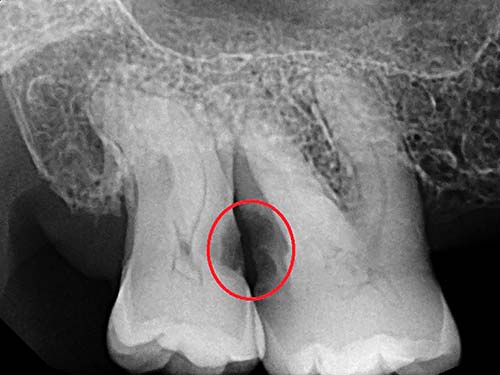

When is tooth extraction necessary?

Tooth extraction is necessary when a tooth is beginning to impede on a patient’s healthy lifestyle. If you’re unable to eat or drink comfortably, and the dentist deems that a filling or root canal offers little value to a patient, we will generally recommend extraction.